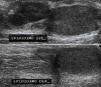

El ultrasonido testicular mostró ambos testículos y epidídimo derecho de tamaño normal, pero el epidídimo izquierdo se observó aumentado de tamaño, de bordes lobulados y bien definidos con dimensiones de 15x7x15mm y con vascularidad central en la modalidad Doppler (fig. 4).